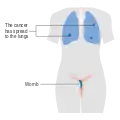

Stage 2 choriocarcinoma Stage 3 choriocarcinoma

Stage 3 choriocarcinoma Stage 4 choriocarcinoma